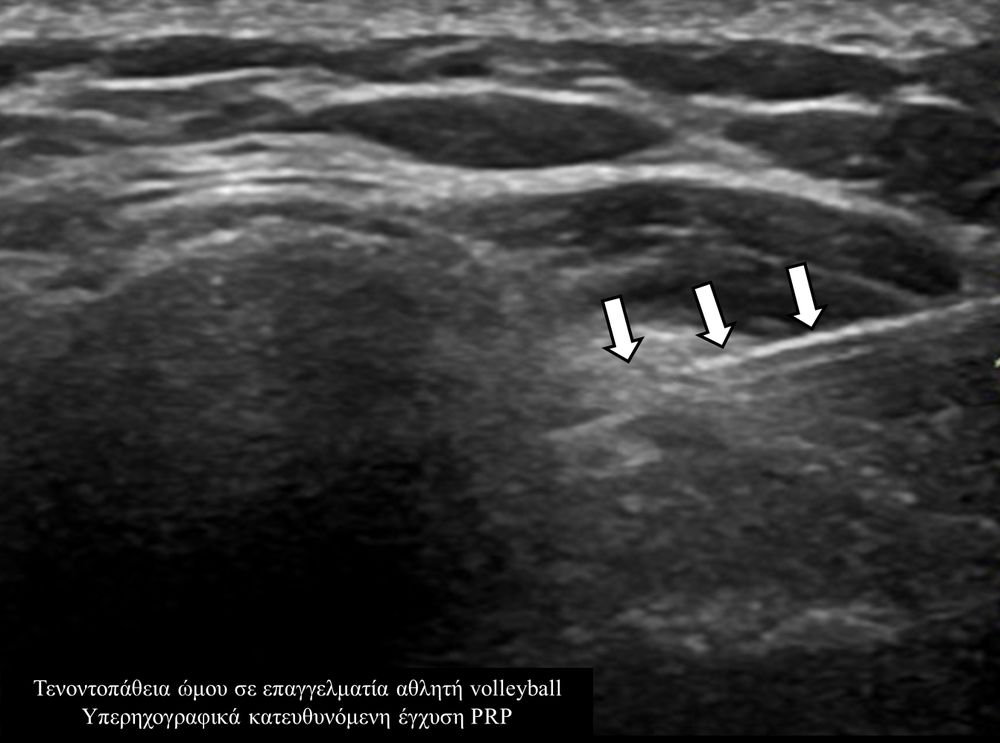

Οι κατευθυνόμενες εγχύσεις σε αθλητικές κακώσειςαποσκοπούν στη μείωση του πόνου, την ενίσχυση της αποτελεσματικότητας της φυσικοθεραπείας και την επιτάχυνση της διαδικασίας επούλωσης για την πιο γρήγορη επάνοδο του αθλητή στις αθλητικές του δραστηριότητες. Η πιο διαδεδομένη έγχυση αποτελεί η έγχυση PRP.Ανήκει σε μια σύγχρονη θεραπευτική μέθοδο γνωστή ως Ορθοβιολογική θεραπεία και βασίζεται την ικανότητα του οργανισμού να θεραπεύεται με τα δικά του αποκλειστικά θεραπευτικά μέσα χωρίς να υπάρξει χρήση φαρμάκων.Το PRP (Platelet Rich Plasma)-πλάσμα πλούσιο σε αιμοπετάλια- σήμερα αποτελεί μια θεραπευτική μέθοδο πρώτης γραμμής με σχετικά μεγάλη επιτυχία για την επούλωση τραυματισμένων τενόντων, μυών και εκφυλιστικών παθησεων όπως οστεοαρθρίτιδα.Η εφαρμογή του περιλαμβάνει μία ευρεία ποικιλία από παθήσεις όπως:

- Οξείες και χρόνιες Τενοντίτιδες και Τενοντοπάθειες (τενοντίτιδα αχιλλείου, επιγονατιδικού,οπισθίων μηριαίων, υπερακανθίου του ώμου)

Η έγχυση γίνεται πάντοτε με την βοήθεια υπερηχογραφικού ελέγχου ώστε να είμαστε απόλυτα σίγουροι για το σημείο έγχυσης τοπικά.